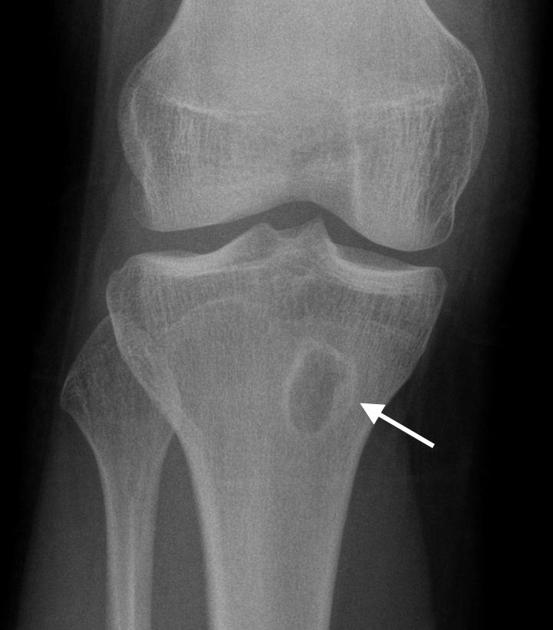

Так на рентгене может выглядеть инфекционное осложнение.

С целью предупреждения распространения инфекции одним из методов лечения является радикальное удаление пораженной фаланги. Такой подход обусловлен низким эффектом антибиотикотерапии даже на фоне применения препаратов, улучшающих кровоснабжение конечности. Вышележащие отделы ноги характеризуются более качественным кровотоком, поэтому лечение назначают согласно стандартному протоколу ведения больных.